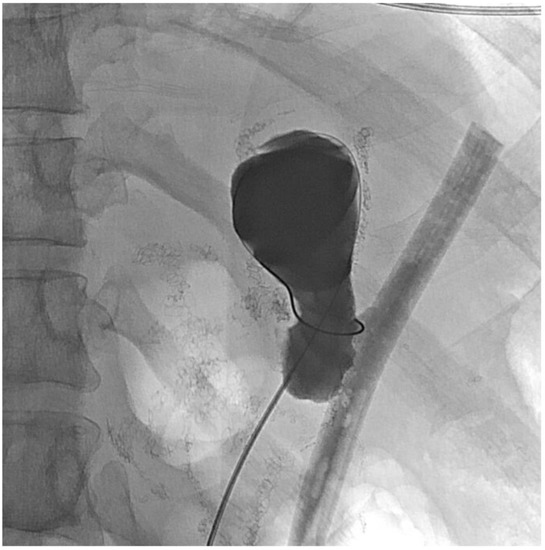

2. Detailed Case Description